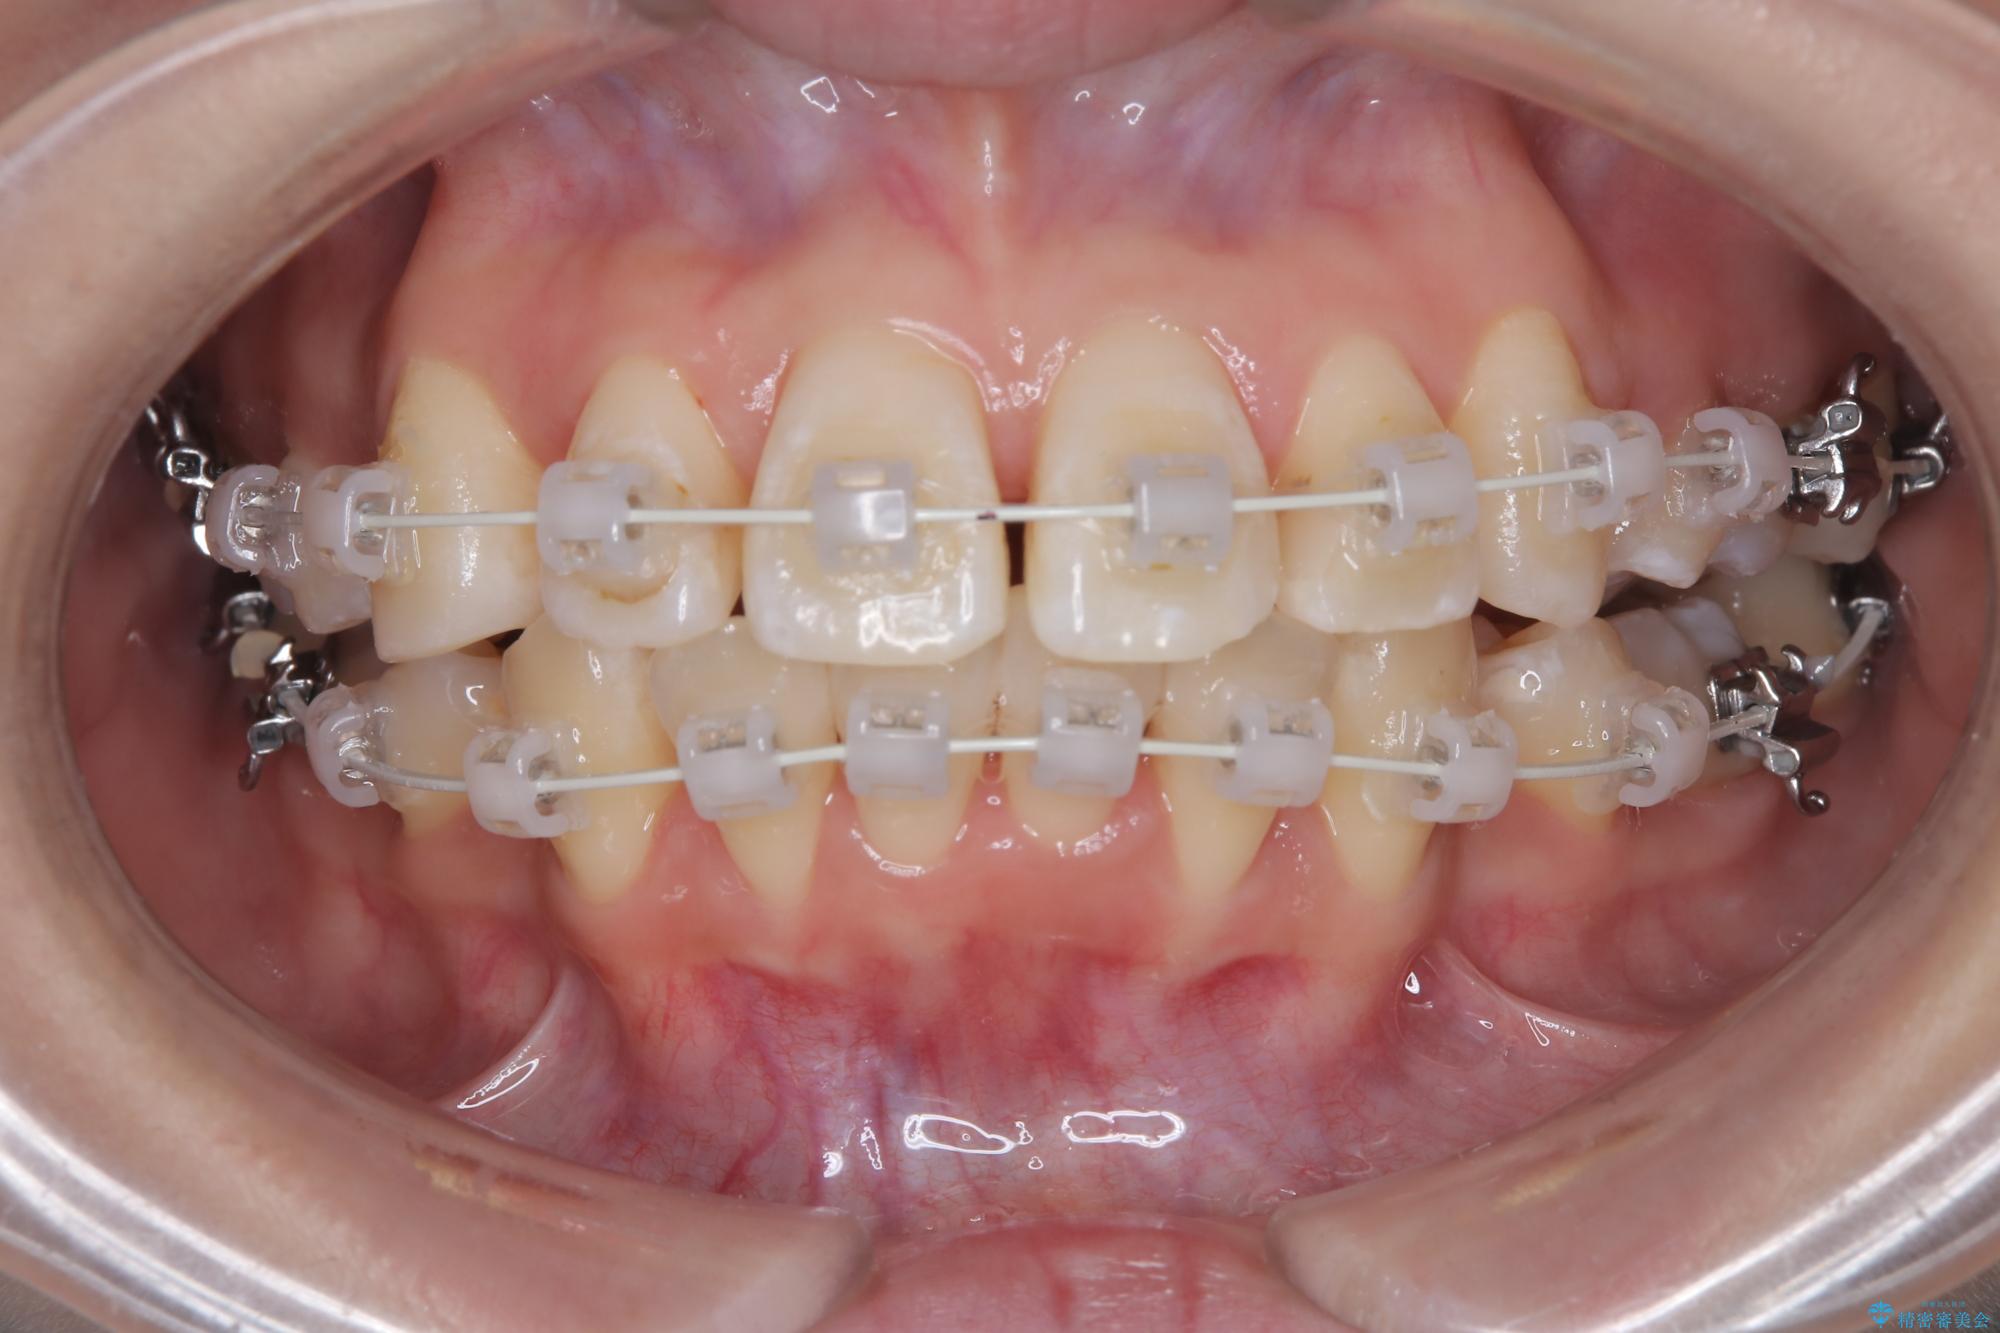

今回の矯正治療では、まず計画通り上下左右の小臼歯4本を抜歯し、八重歯や正中のズレを解消するための十分なスペースを確保しました。装置には、目立ちにくい白いブラケットとワイヤーを使用した審美ワイヤー矯正を採用。

抜歯によってできたスペースを利用し、

八重歯: 突出していた八重歯を歯列内に誘導し、デコボコを解消しました。

正中のズレ: 歯を左右対称に移動させることで、上下の歯の中心線を正確に合わせ、顔全体のバランスも改善しました。